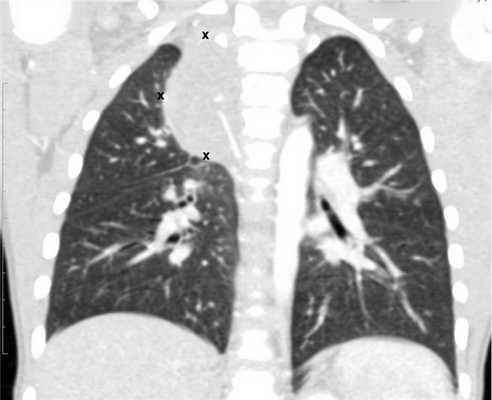

- Рентгенография органов грудной клетки (данное обследование обязательно, потому что оно дает возможность подтвердить диагноз при первичных новообразованиях средостения и наличии метастазов в легких).

- КТ (расшифровка: компьютерная томография), МРТ (расшифровка: магнитно-резонансная томография), ПЭТ-КТ (расшифровка: позитронно-эмиссионная томография, совмещенная с КТ). Эти обследования необходимы, чтобы рассмотреть структуры организма послойно и визуализировать опухоль. Они показывают, как сильно распространен патологический опухолевый процесс на находящиеся рядом ткани и органы, есть ли поражение костей. КТ - это самый чувствительный метод для обнаружения метастазов в легких. Проведение МРТ и КТ головного мозга необходимо, чтобы обнаружить и визуализировать герминогенные новообразования эпифиза.

![Метастазы в легких до лечения и после 4х циклов химиотерапии по схеме «ВЕР» (КТ грудной клетки)]()

Метастазы в легких до лечения и после 4х циклов химиотерапии по схеме «ВЕР» (КТ грудной клетки)